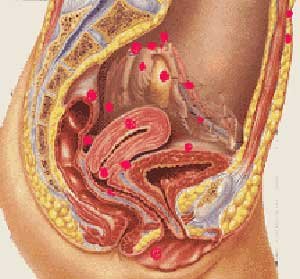

子宫内膜异位症是一种高发性的激素依赖性的疾病,常见于育龄妇女。据相关的报道,它在育龄妇女中的发病率约为10%,为广大的女性带来了巨大的痛苦。更加严重的是子宫内膜异位还可能引发其他的并发症,那么子宫内膜异位症的并发症有哪些呢?泉州玛丽医院的专家为您详细介绍。

子宫内膜异位症的并发症有哪些呢?游走的子宫内膜常移到盆腔、卵巢、子宫直肠陷窝,也可到达膀胱、肺等地方。游走的子宫内膜与“家乡的”子宫内膜一样,随着体内激素的变化,可出现局部的剥脱出血,似月经来潮,每月一次,也可出现相应部位的症状,如周期性血尿、周期性咯血及周期性腹痛等。

子宫内膜异位症的并发症有哪些呢?移位的子宫内膜惹的祸可不少:

疼痛:

是最常见的症状之一,以下腹及腰骶部疼痛最为明显,常于月经来潮前1—2天开始,经期第一天最严重,以后逐渐减轻。但是随着病期的延长,经期腹痛会更加明显。

不孕:

占子宫内膜异位症的40%-50%。内异症可使盆腔粘连、输卵管坚硬甚至梗阻、激素的代谢功能异常及免疫功能异常,导致孕卵逆行与子宫内膜不同步,或使孕卵本身逆行受阻而发生不孕。

异位妊娠(宫外孕):

异位的子宫内膜可以引起盆腔粘连,输卵管运行障碍,受精卵只有在局部种植发育,导致异位妊娠的概率增加。

月经失调:

受异位的子宫内膜侵犯,卵巢实质组织被破坏,使激素代谢受影响,出现月经紊乱和经期阴道流血增多,个别还会出现经前期点滴出血。

性交疼痛:

异位的子宫内膜使周围组织肿胀,当性交时由于受阴茎抽动的影响,引起疼痛,以月经前期较为明显。

子宫增大:

子宫内膜可以“移位”到子宫肌壁内,使子宫增大,每当月经来潮时,子宫肌壁间的内膜也受激素的影响,发生出血,引起疼痛,非常痛苦。

卵巢肿瘤:

卵巢是异位的子宫内膜最爱“居住”的场所,每当月经来潮,经血总会在卵巢存留,而且会越存越多,慢慢地包块就不知不觉地形成了,随着月经周期的变化,包块可以时大时小,包块里面存积的血液渐渐增加,由于存积的血液日久变质,红细胞被破坏,故当切开包块时,所见的内容物酷似巧克力,这在医学上称为“巧克力囊肿”。